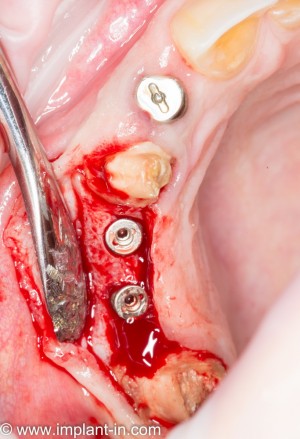

![02[1]](http://2026.implant-in.com/wp-content/uploads/2015/08/021-300x296.jpg) |

![03[1]](http://2026.implant-in.com/wp-content/uploads/2015/08/031-300x304.jpg) |

однако, этот метод связан с одним неприятным моментом, а именно — необходимостью донорского участка, из которого производится забор аутокостного фрагмента. Другими словами, это относительно травматичная методика. Но она не требует использования биоматериалов и, при правильной адаптации аутотрансплантата — барьерной мембраны, отличается высокой надежностью, предсказуемостью и низкой себестоимостью.

У меня нет ипотеки и других долгов, поэтому я принимаю решение разбить весь объем хирургического лечения на четыре этапа — по одному в каждом из сегментов зубного ряда. И начинаю я… угадайте, с какого участка? Верно, с того, который уже не функционален из-за критического разрушения зубов — с левого нижнего:

Операция заняла всего 60 минут, послеоперационные явления были настолько незначительны, что пациентка чуть ли не через пару недель решилась на вторую операцию: